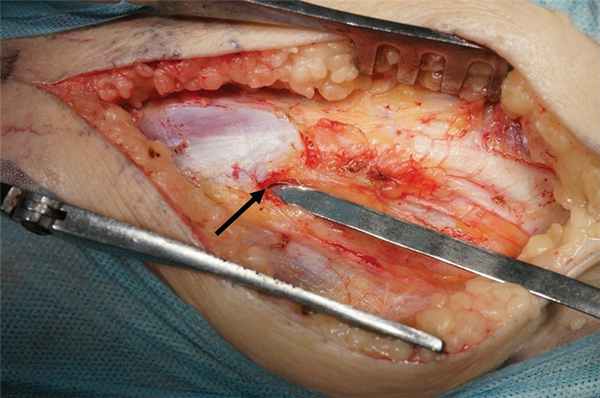

При интраоперационной ревизии основными причинами компрессии нерва являлись уплотненная поверхностная фасция, покрывающая нерв на уровне головки малоберцовой кости (рис. 1), и уплотненная фасция длинной малоберцовой мышцы (наружный и внутренний листки), которая формирует фибулярную арку на уровне перегиба нерва через малоберцовую кость и входа в малоберцовую мышцу (рис. 2).

Рис. 1. Интраоперационая фотография.

Стрелкой обозначена стенозированная фибулярная арка.

Рис. 2. Интраоперационная фотография.

Стрелкой обозначена утолщенная поверхностная фасция, перекидывающаяся с головки малоберцовой кости на латеральную головку икроножной мышцы.